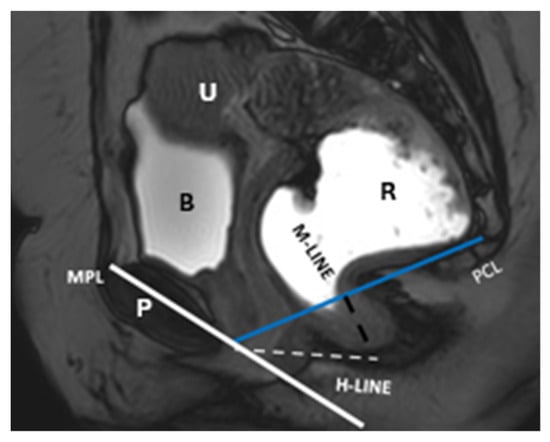

| Pubococcygeal Line (PCL) | Line from the inferior pubic border to the last coccygeal joint | Baseline for measuring organ descent | PCL Compartment Staging Stage 0: Above PCL Stage I: Descent <3 cm below PCL Stage II: Descent 3–6 cm below PCL Stage III: Descent >6 cm below PCL Stage IV: Complete organ prolapse |

| H Line (Hiatal Line) | Distance between the inferior pubic border and the anorectal junction | Assesses puborectal hiatus (anteroposterior dimension during straining) | POP Grade Hiatal Enlargement Normal: <6 cm Mild: 6–8 cm Moderate: 8–10 cm Severe: >10 cm |

| M Line (Muscle Line) | Perpendicular line from the PCL, measuring organ descent | Evaluates posterior pelvic organ descent | Pelvic Floor Descent Normal: <2 cm Mild: 2–4 cm Moderate: 4–6 cm Severe: >6 cm |

| Anorectal Angle | Angle between the posterior distal rectum and the anal canal’s central axis | Reflects the levator ani muscle function during contraction | 108–127° at rest, decreases by 15–20° during contraction |